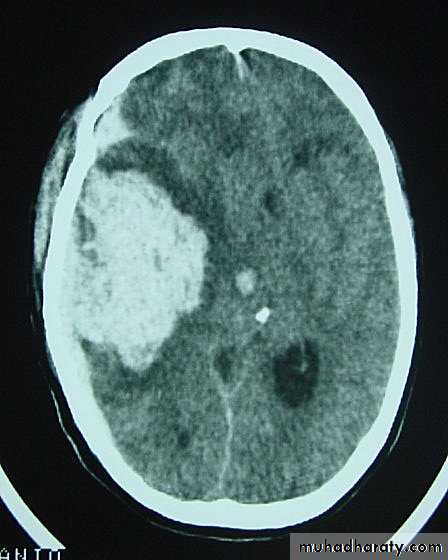

c. Intracerebral Haematoma

This is the least common of traumatic haematoma.They are due to areas of traumatic contusion coalescing into a contusional haematoma.

Disrupted cerebral tissue release thromboplastins that potentiate haemorrhage.

CT scan: appear as hyperdence lesions with associated mass effect and midline shift.Large intracerebral haematomas should be evacuated unless the patient’s neurological state is improving.

Small inracerebral haematomas may not require removal, but be aware that they can expand.